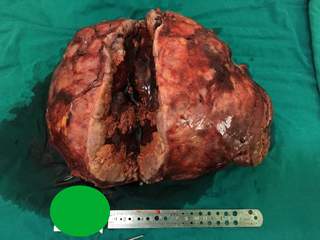

经过反复论证和精心准备,陈敏山教授团队在麻醉科曾维安主任、李强主治医师的配合下于2015-12-24上午为患者实施了精准肝癌切除术。人字形腹部切口探查可见肿瘤位于右肝,向下延伸盘踞右侧腹腔,与大网膜广泛粘连,血供丰富,分离较为困难,术中B超可探及门静脉右前支癌栓,进过三个小时“血雨腥风”地埋头苦干,完整切除肝脏肿瘤,并切开门静脉取尽了癌栓。整个手术过程出血约2000毫升,肿瘤切除大体30*30*25cm,重量3.5kg,瘤内大量出血坏死,门静脉可见癌栓。由于术前准备充分,术中监控到位,术后恢复非常顺利,患者第二天下床活动,术后7天肝功能基本恢复正常,十天后拆线出院。